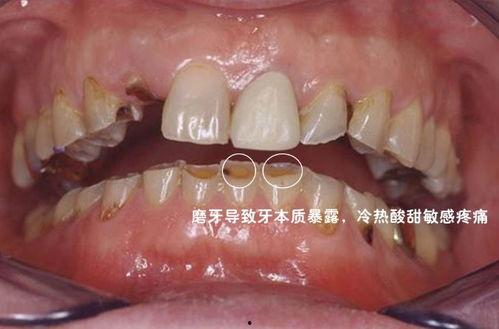

磨牙不仅会影响睡眠质量,还可能导致牙齿磨损、颞下颌关节疼痛等问题。而网络上的成人磨牙实录视频大全图片,正是这些磨牙者的真实写照。